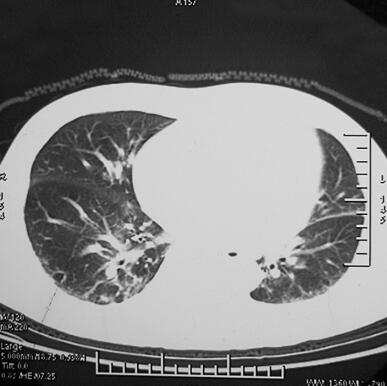

4月2日胸部CT(图1)示双肺见小片状高密度影,以右肺为著,双侧胸腔积液,少量心包积液。痰培养未找到致病菌,4月4日调整抗生素,给予美罗培南1.0g,每12小时1次,静脉滴注抗感染治疗。同时多次查血生化,血Na+均显著降低,多波动于105~115mmol/L,并伴有神志淡漠,予以限水及补钠未见效。为明确顽固性低钠血症的原因,与内分泌科讨论后行血ACTH、皮质醇节律及24小时尿钠定量。结果显示患者血ACTH及血皮质醇均明显低于正常,24小时尿钠在正常范围内,考虑存在腺垂体功能减退症,行垂体MRI及甲状腺功能检查。垂体MRI示空泡蝶鞍,甲状腺功能正常。遂给予氢化可的松100mg静脉滴注,每日2次,4月18日复查血生化K+ 4.53mmol/L,Na+ 130mmol/L,Cl− 98mmol/L,当天停用美罗培南,改为莫西沙星0.4g静脉滴注,每日1次,连续应用3天。4月25日复查胸部CT(图2)示感染征象已控制,准予出院。

图2 4月25日胸部CT